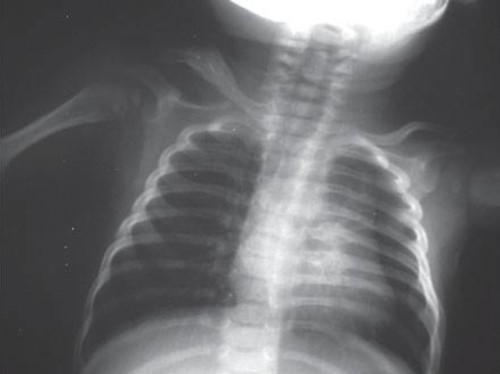

Common X-ray Findings: